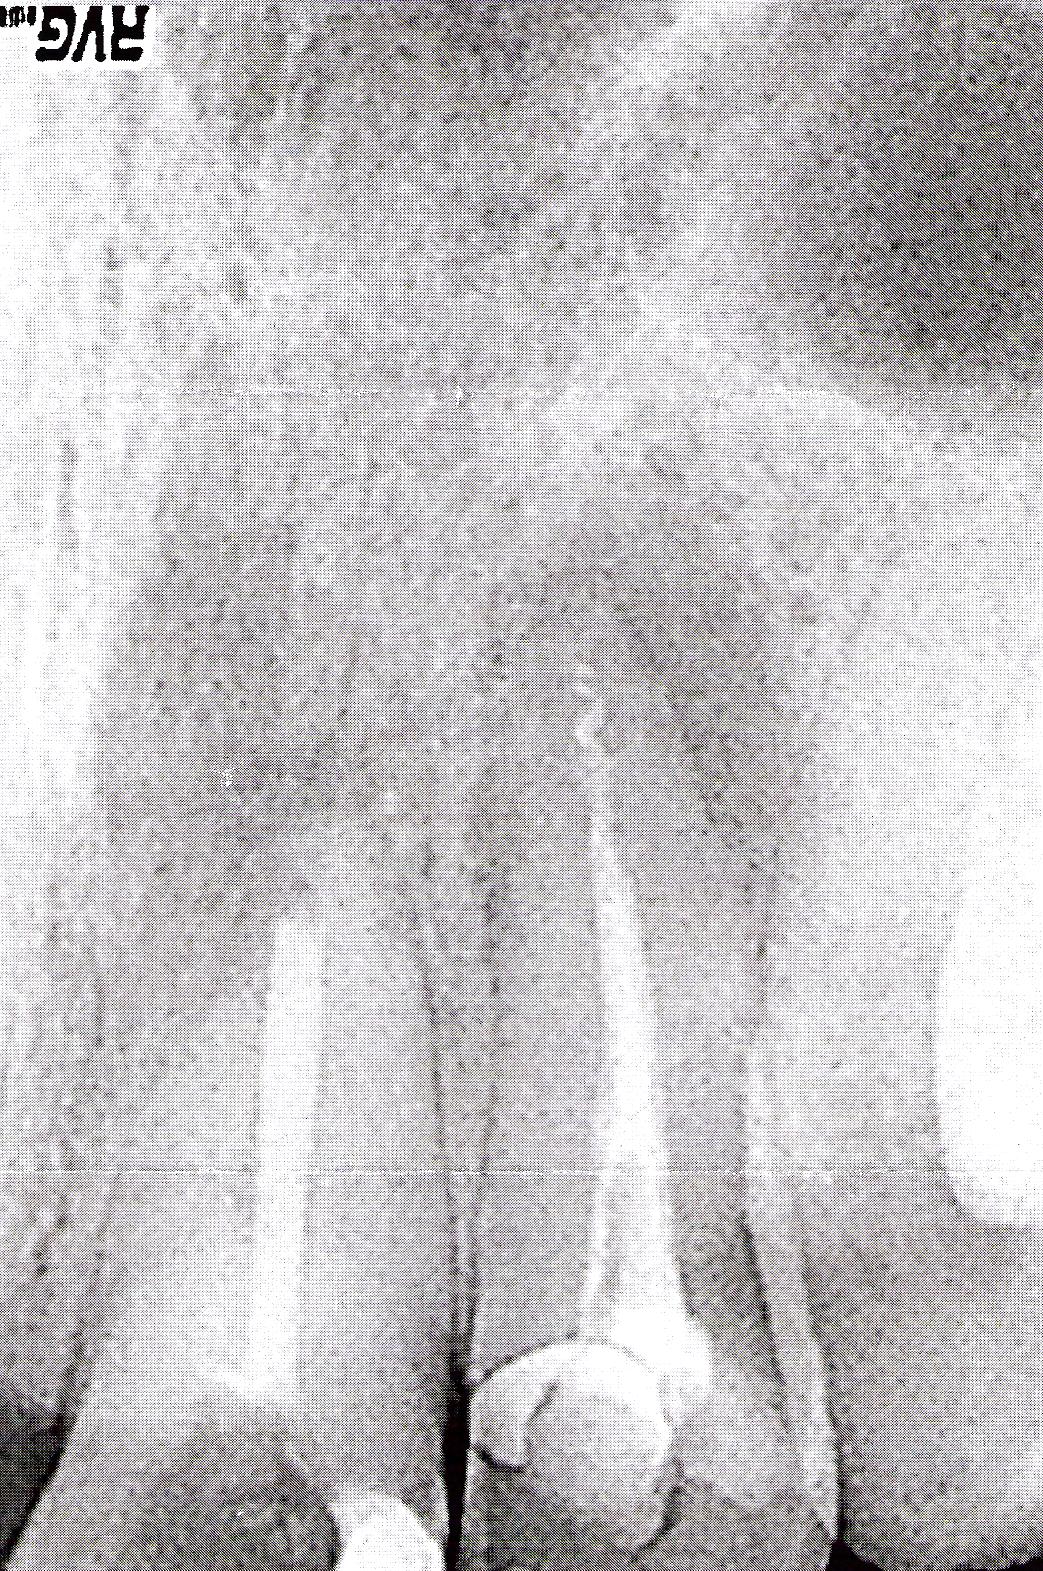

Sig. Carlo, Ci racconta una storia clinica vissuta. Dalla radiografia sembrerebbe che nel canale dell’incisivo laterale, ci sia la presenza di uno strumento canalare. Altri colleghi con esperienze maggiori di endodonzia, potranno confermarlo. Si tratta di una complicanza che a volte può avvenire. Questa potrebbe essere la causa delle ripetute infezioni. Consiglio di ritrattare i canali asportando l'eventuale strumento canalare, se la cura non è effettuabile o non da risultati, non resta che passare all'apicectomia, in cui suggerisco l'esame istologico dei tessuti rimossi.

Caro Signor Carlo, le Rx non sono ovviamente chiare...ma nel laterale sin. c'è uno strumento canalare fratturato (sembra), nell'Incisivo centrale c'è una chiusura dubbia per il materiale usato ...in ogni caso ha poca importanza...quello che è certo è che entrambi i denti hanno una evidente osteolisi periapicale...che è segno di infezione...che poi sia granuloma o cisti...poca importanza ha, dal punto di vista pratico-terapeutico. Cosa fare: 1- Bisogna iniziare almeno tre giorni prima di intervenire una copertura antibiotica con un antibiotico potente, a largo spettro soprattutto su anaerobi gram neg. come il ceftriaxone bisodico in fiale intra muscolari da 1Gr. (una al di per tutto il trattamento e proseguire oltre di almeno 4/5 giorni. (ovviamente è solo un suggerimento ...non posso prescrivere antibiotici per vie web senza neanche averla vista e fatto una anamnesi accurata...lo farà il suo medico che la prenderà in cura)!!!!Faccia la prima seduta un lunedì...la seconda un Venerdì e la terza di chiusura dei canali il Lunedì sucessivo...in modo da assumere , partendo da tre giorni prima e terminando 4/5 giorni dopo, in tutto 14/15 Fiale da 1 Gr. (una al dì) 2- Bisogna aprire entrambi i denti e procedere ad una rimozione dello strumento canalare fratturato (lo si può fare con una certa tranquillità)3- Bisogna rimuovere le vecchie terapie canalari e procedere alla strumentazione accurata con lavaggi (sotto diga ovviamente) di ipoclorito neutralizzato poi da acqua ossigenata e lavaggi soprattutto prima della chiusura provvisoria a fine seduta con prima Clorofenolocanforato, poi con lo stesso antibiotico lasciato dentro il canale. Si chiudono poi i denti alla fine di ogni seduta con membrana osmotica per impedire la reinfezione dei denti coi microbi da fuori a dentro e nello stesso tempo per fare uscire il gas prodotto dai microbi sopravvssuti dentro che causerebbe pressione e quindi dolore! E qui finisce la prima seduta! 4-Nella seconda seduta si rifinisce la strumentazione... si vede se c'è pus ( se c'è bisogna progammare altre sedute) si ripete tutto e si chiude sempre con membrana osmotica... 5-infine in terza seduta si chiude il dente e poichè le tante terapie canalari fatte rendono impossibile il sigillo apicale, si procede contemporaneamente ad una retrograda con chiusura dei due apici con amalgama chirurgica priva di zinco ...inerte...dopo aver preparato gli apici ad accoglierla. Si tratta chirurgocamente il tramite osseo con lavaggi dello stesso antibiotico ma in forma endovenosa usata però localmente per lavare l'osso, con fibrina artificiale e osso artificiale e eventualmente una membrana si risutura il lembo ed è tutto finito! ATTENZIONE- questa è la procedura...ma si deve mettere nelle mani di un eccellente endodontista ... che potrà variare la tecnica...che però in linea di massima è questa! ... solo in caso di insuccesso...improbabile se eseguito tutto bene...può ricorrere all'implantologia...questo è il mio consiglio...cordialmente (e si ricordi l'antibiotico DEVE ESSERE QUELLO ma dopo accertamento accurato del Dentista e del MEDICO (che devono collaborare parlandosi...dico che l'antibiotico è queto perchè nella mia lunga esperienza è il solo che ha dato risultati pressocchè costanti...in una zona in cui pochissimi antibiotici agiscono!!! ancora cordialmente

Signor Carlo, non penso assolutamente che i colleghi che si sono avvicendati al ritrattamento conalare, soprattutto un'endodontista, non siano capaci di risolvere due canalari facili come quelle degli incisivi, pertanto ci deve essere un altro problema, francamente la Rx. che ha mandato è poco leggibile e non mi sembra ne un lentulo e ne altro strumento canalare, visto la densità del materiale che sembrerebbe fratturato, perchè mi risulta poco compatto e denso anche ad ingrandimenti maggiori. Le consiglio di ritrattare i canali in questione o in alternativa, visto il calvario e la sofferenza tissutale dell'osso periapicale, di inserire due impianti post-estrattivi a carico immediato. Per saperne di più legga appunto il caso clinico da me pubblicato: impianti post-estrattivi a carico immediato, e si sentirà rinascere. Cordiali saluti e sono a disposizione per qualsiasi chiarimento o commento.

Beh, la rx non è molto chiara ..da quel poco che riesco a vedere i due granulomi presenti sono decisamente estesi e probabilmente ormai la reazione apicale infiammatoria cronica si è anche iscistata. La conseguenza di ciò è che ben difficilmente con una terapia canalare ( a parte il calvari già passato ) potrebbe ristabilire la salute della zona periapicale. Il consiglio di valutare le avulsioni e la sostituzione con impianti è sicuramente da prendere in considrazione. A mio avviso però, in questo caso, sarebbe meglio estrarre, far guarire ed eventualmente rigenerare la parte mancante di osso, se le cisti avessero eroso l'osso vestibolare, e solo successivamente posizionare gli impianti. Nel periodo intermedio, dei provvisori posticci, tipo meryland le permetterebbero di avere una normale vita di relazione. Cordiali saluti